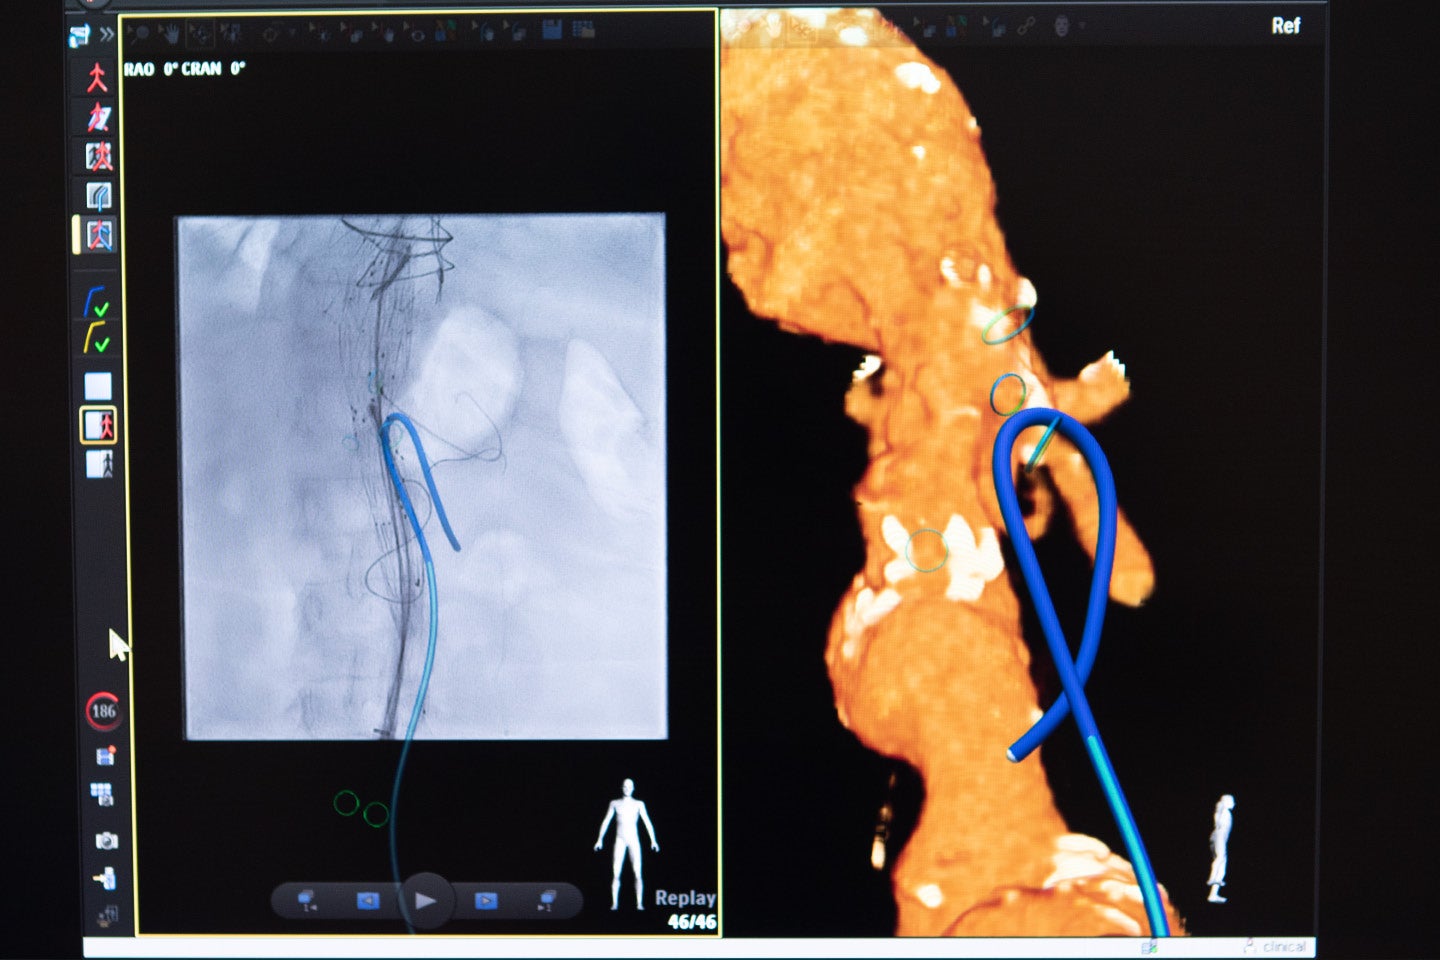

At UMass, Schanzer is using a minimally invasive procedure called the fenestrated endovascular aortic repair, allowing surgeons to repair the aorta through small incisions in the groin or arms while still preserving blood flow to the critical branch arteries in the kidneys and other vital organs of the body.

Schanzer said one of the most exciting advancements in vascular surgery is the use of Fiber Optic RealShape technology.

UMass became the first hospital in the U.S. to use this fiber optic light imaging to guide the aortic repair surgeries rather than relying on radiation, eliminating the large doses of X-ray radiation traditionally needed for the surgery.

“I would say that during my career, fenestrated and branched endografts, which are these advanced grafts we can use to treat these complex aneurysms, and Fiber Optic RealShape technology are the two most significant technological innovations I have seen across the entire field of surgery,” Schanzer said.